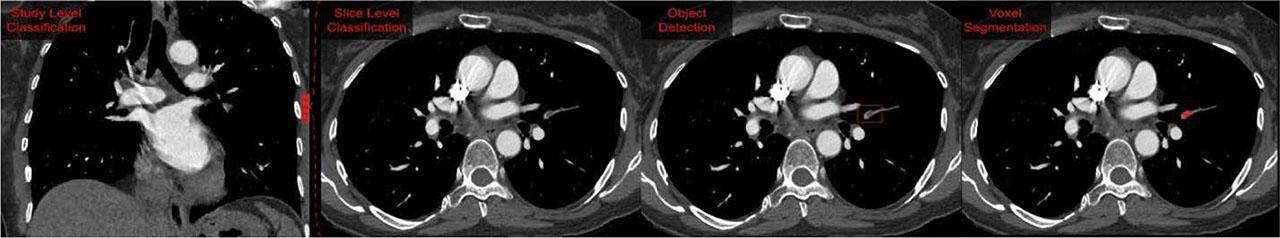

FIGURE 1.